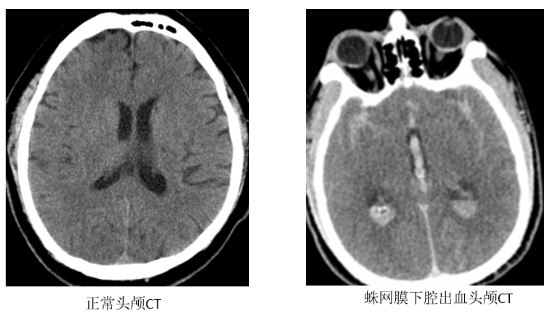

蛛网膜下腔出血是什么?

我们的大脑表面覆盖着三层保护膜,像三明治一样。中间那层薄薄的、像蜘蛛网一样的膜叫“蛛网膜”。

它和紧贴大脑的那层膜之间的空隙,就是“蛛网膜下腔”,里面流淌着营养大脑的脑脊液。

当这个腔隙里突然进了血,就是蛛网膜下腔出血。血液像化学刺激物一样,会引发大脑血管剧烈痉挛和全身强烈反应。

CT检查:首选,能快速判断大脑周围有没有出血。